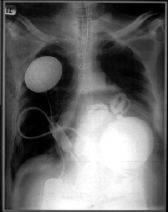

health_heart_luEl corazón experimental, del tamaño de una pelota de softbol, llamado Ahincor, fue implantado el 2 de julio al enfermo, por ambos cirujanos de la Universidad de Louisville, en una operación que duró siete horas.

El corazón, una bomba de plástico y metal hecha por la empresa Abiomed Inc. de Danvers, en Massachusetts, cuenta con una batería interna y un controlador que regula la velocidad de bombeo. Una batería externa alimenta el artefacto transmitiendo electricidad a través de la piel. La batería interna, del tamaño aproximado de un radiolocalizador, permite el funcionamiento del corazón hasta por 30 minutos sin recarga.